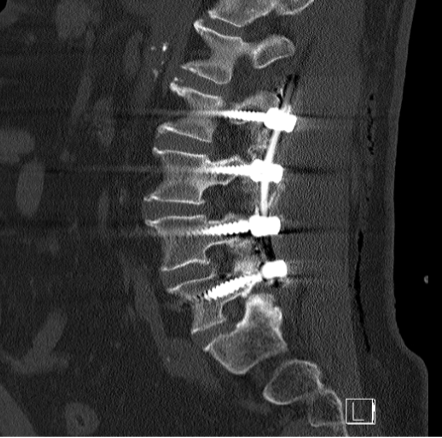

Üç yıl kadar önceki bu muayene ve tetkikler sonucunda Akın Bey, bana “henüz ameliyat safhasında değilsiniz, biraz daha fizik tedavi ve ağrı kesicilerle devam edelim” demişti. O günkü radyolojik tetkiklerde L4-L5 bölgesinde “lomber spinal stenoz” tabir edilen kanal daralmasından bahsediliyordu aslında. Bunun lomber dar kanal (spinal stenoz) ve buna eşlik eden spondilolistezis olduğu ifade edildi. Ben anlatması kolay olsun diye sinirlerin geçtiği omurga kanallarının daralması diyorum.

Ameliyatın bazı safhalarının video kaydını seyrettim daha sonra. Ne kadar hassas ve ince bir işlem olduğunu bir kere daha müşahede etmiş oldum. Omurgada milimetrenin küsurları bile önem kazanıyor. Oraya metallerin yerleştirilmesi büyük bir hassasiyet gerektiriyor. Akın Hoca bana ‘iğne ile kuyu kazmaya benzer bizim omurga üzerindeki işlemlerimiz’ demişti. O bakımdan doktorlar az da olsa bir endişe içinde ameliyatı sona erdiriyorlar ama ilk fırsatta bu metallerin yerli yerinde olup olmadığını ve omurga kanallarındaki daralmanın giderilip giderilmediğini görmek istiyorlar. Bu sebeple beni sabah saat 05.30’da gelip tomografiye götürdüler ve ortaya çıkan neticeyi görmek istediler. Daha sonra odama gelen Dr. Akın Bey ve arkadaşları yerleştirilen metal parçacıklarının tam istedikleri konumda olduğunu gördüklerini söylediler ve beni rahatlattılar. Şu anda omurgamda dört adet bir tarafta, dört adet diğer tarafta olmak üzere sekiz metal parçası taşıyorum. Yani omurgama yerleştirilen vidalar ve sabitleyici metal çubuklarla geziyorum.

Ameliyatın üzerinden iki buçuk ay geçtikten sonra Dr Akın Hocaya gittim kontrol için. Yeniden tomografi çekildi. Hoca, her şey yolunda dedi ama beni kemik erimesi kaygısıyla başka bir uzmana yönlendirdi. ‘Bu bir tedbirdir’ diye de vurguladı. Şimdi onun neticelerine de bakarak korseyi daha ne kadar taşımam gerektiğine karar verecek.